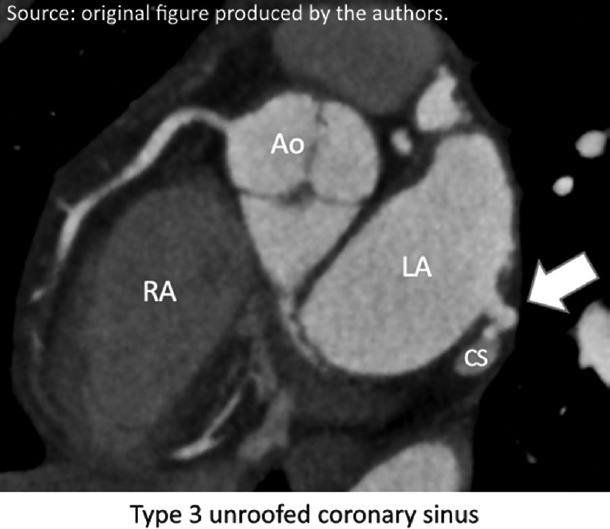

大约25%-40%的缺血性中风是隐源性的,尽管进行了彻底的评估,但仍无法确定病因。隐源性中风背后的机制通常是栓塞性的,经常起源于隐匿的心脏来源。无顶冠状窦(UCS)是一种罕见的先天性异常,涉及冠状窦顶部部分或完全缺失,导致左心房和冠状窦之间的连接。这种缺陷可以是无症状的,也可以表现为分流引起的矛盾栓塞等症状。我们报告一位70岁男性患者,有长期胸痛和神经系统症状史,后来通过心脏计算机断层扫描(CCT)诊断为UCS (III型和IV型)。心泡试验证实右至左分流,经胸超声心动图未发现。该病例强调了在诊断隐源性卒中时考虑先进成像技术(如CCT)的重要性,因为超声心动图可能由于心脏后部结构的可视性差而遗漏缺陷。

Around 25%-40% of ischemic strokes are cryptogenic, with no identifiable cause despite thorough evaluation. The mechanisms behind cryptogenic strokes are often embolic, frequently originating from occult cardiac sources. An unroofed coronary sinus (UCS), a rare congenital anomaly, involves a partial or complete absence of the coronary sinus roof, leading to a connection between the left atrium and the coronary sinus. This defect can be asymptomatic or present with symptoms such as paradoxical embolism due to shunting. We present the case of a 70-year-old male with prolonged chest pain and a history of neurological symptoms, who was later diagnosed with a UCS (types III and IV) through cardiac computed tomography (CCT). A cardiac bubble test confirmed a right-to-left shunt, which was not detected on transthoracic echocardiography. This case underscores the importance of considering advanced imaging techniques such as CCT in the diagnosis of cryptogenic stroke, as echocardiography may miss defects due to poor visualization of posterior cardiac structures.